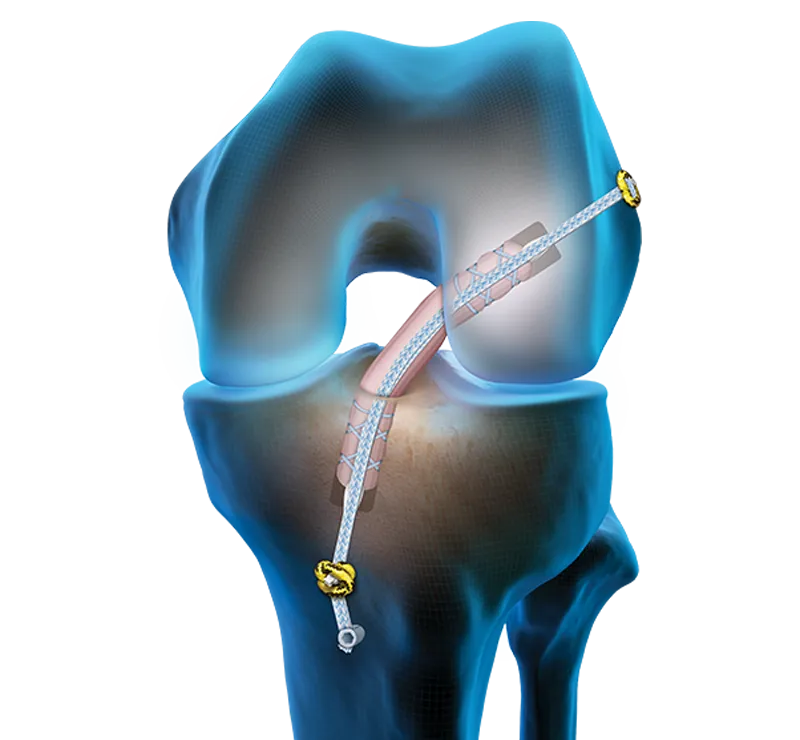

When your ACL needs to be repaired or reconstructed, your surgeon will use an implant either to reattach your ACL to the bones of the knee (in a repair) or to attach a graft that serves as your new ACL to the bone (in a reconstruction).

While traditional implants for ACL repair and reconstruction use metal screws or buttons, the TightRope SB implant is made entirely of suture, which is a soft, strong fiber. Instead of the metal button or screw, the suture bunches down onto your bone and forms a “button” to securely fix your ligament in a repair or the new ligament in a reconstruction.

In ACL reconstruction, the damaged ligament is removed from your knee and replaced with a graft, either from your own body (autograft) or from a donor (allograft). There are several types of grafts to choose from, based on your needs.

Arthrex ACL reconstruction uses an "all-inside" technique that is less invasive than other reconstruction options because fewer tunnels are drilled into your knee.